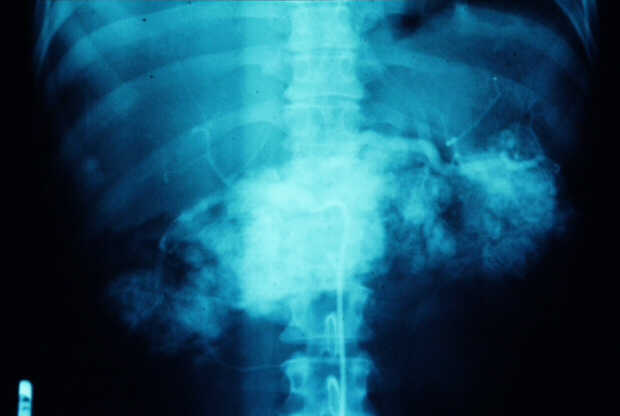

Diagnosis: Angiography

Giuseppe Morelli Coppola, Raffaella Niola, Franco Maglione

Unità Operativa di Radiologia Vascolare ed Interventistica, Azienda Ospedaliera "A. Cardarelli". Napoli, Italy